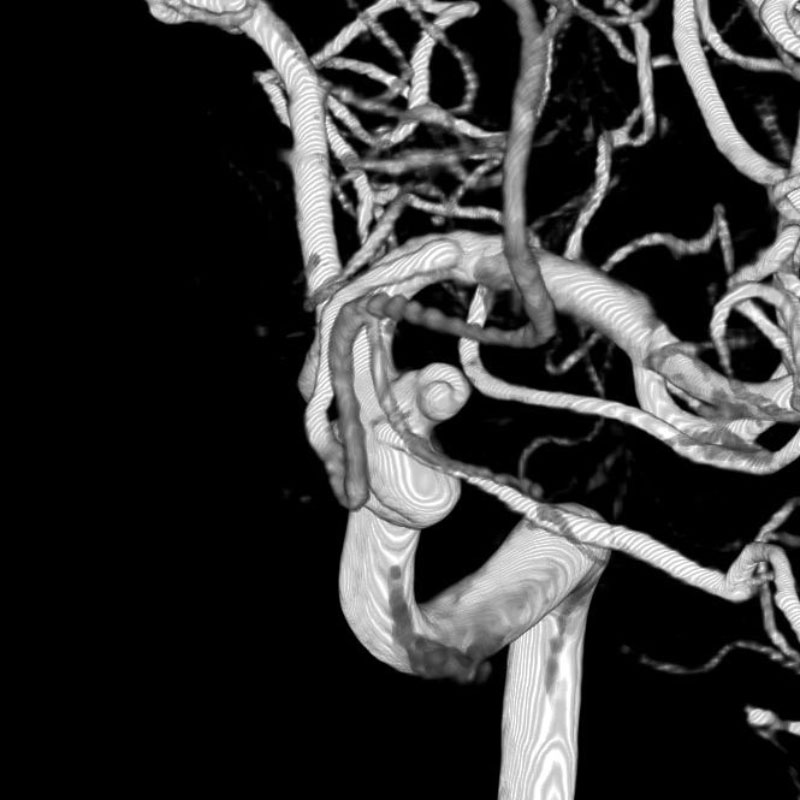

後頭蓋窩髄膜腫

血管塞栓術

芝野/野本